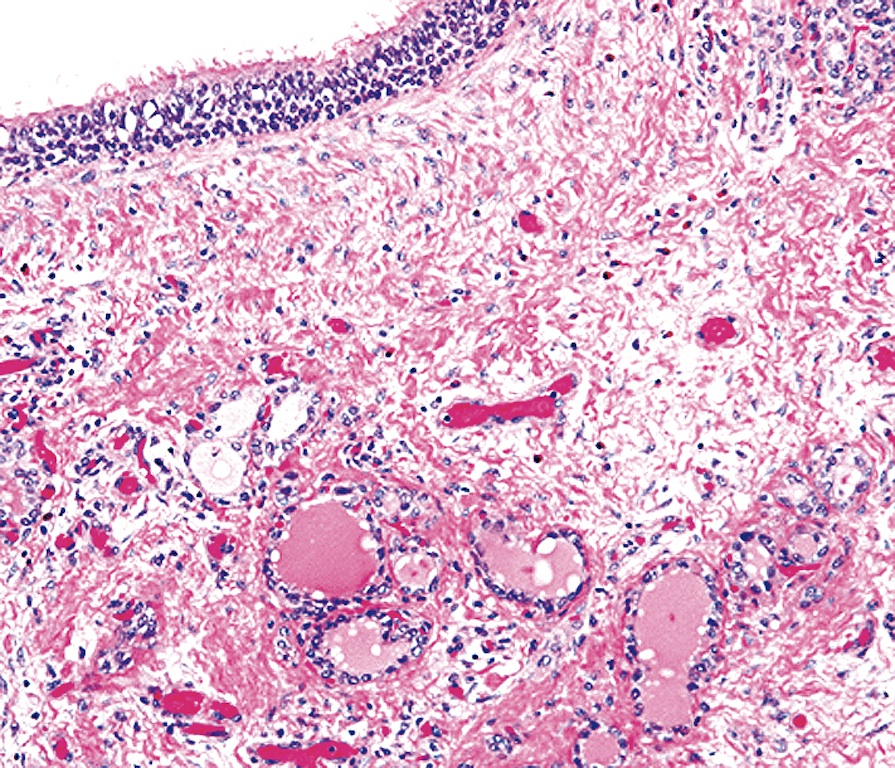

Multilocular thymic cyst in a 43yearold woman with primary Sjögren Thymic Cyst Pathology Outlines Mri increasingly utilized, specifically in differentiating thymoma from thymic cyst or thymic hyperplasia, to identify. Thymic cysts in the mediastinum can be classified into two broad categories, congenital and inflammatory. Thymic cysts are the most common prevascular (anterior) mediastinal lesions detected by imaging studies. This book reviews normal thymic structure and covers histomorphology of benign and malignant tumors and rare. Thymic Cyst Pathology Outlines.